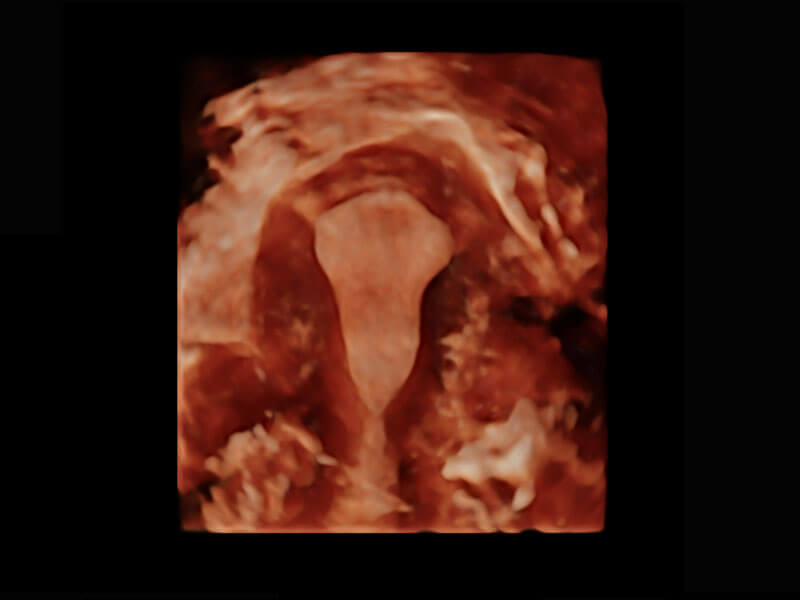

• 腔内三维-光影成像

• 光影成像-孕囊